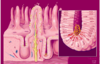

·So blood is flowing toward the central vein (i.e. toward the black star shape), whereas the bile, which is begin formed in these bile canaliculi, here indicated sort of diagrammatically as this green stuff, flows toward the portal tract.

·So the secretion of bile into ducts is an exocrine function, and the secretion of albumin, lipoproteins, IgF1 in response to growth hormones – things like that into the blood are going to be the endocrine functions of the liver, and – as this points out – blood and bile flow in opposite directions in the lobules of the liver.

sinusoidal capillaries

what we call sinusoidal capillaries that are found at either side of hepatocytes (2).